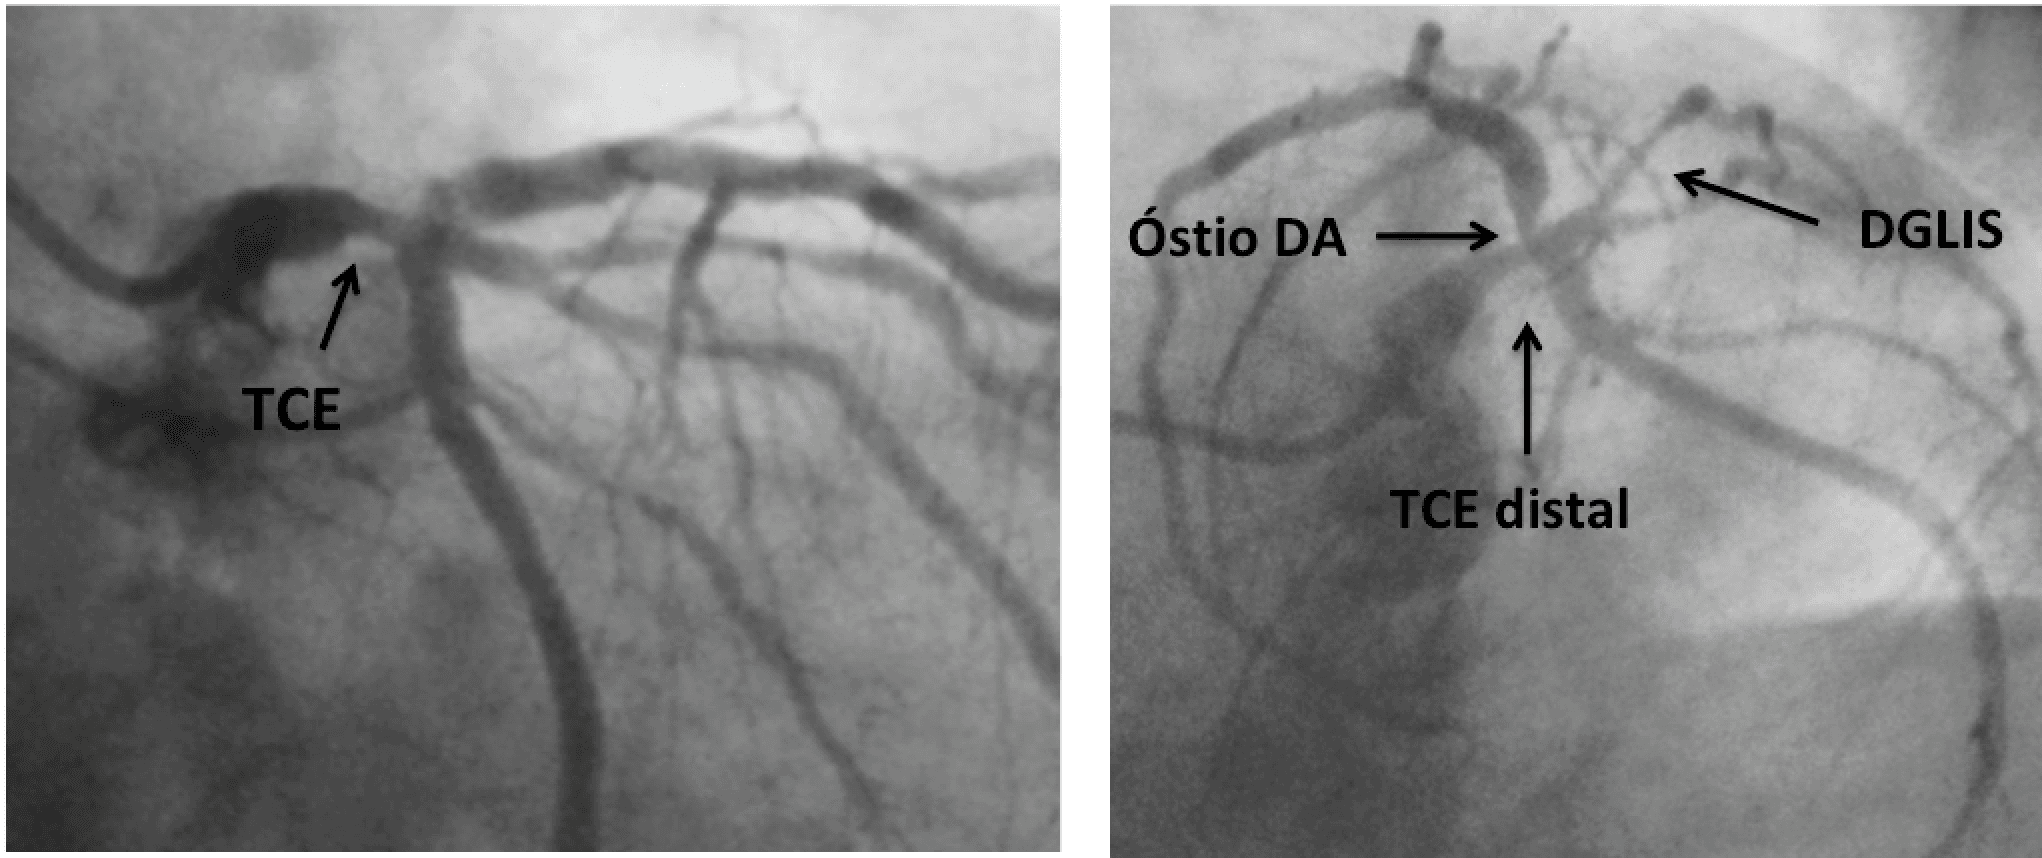

Enquanto a Copa do Mundo 2022 começava no Catar, era publicada no JACC uma revisão campeã sobre o estado da arte na abordagem da doença de tronco da coronária esquerda significativa, isto é, com esten…